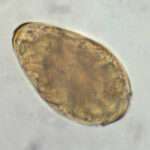

Una vez que la infección avanza y se desarrollan características patológicas más evidentes, el diagnóstico se confirma mediante la identificación de los huevos característicos de los parásitos en muestras de heces o en los contenidos duodenales o biliares. La prueba de Kato-Katz, que es ampliamente utilizada en la detección de parásitos intestinales, permite la observación de estos huevos en las heces. Aunque la prueba es efectiva, su sensibilidad aumenta considerablemente si se realizan varias repeticiones, ya que la cantidad de huevos en una muestra puede ser baja en infecciones leves o tempranas, lo que puede llevar a falsos negativos si se realiza solo un examen.